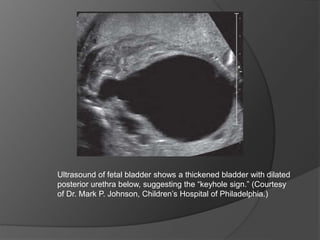

The pathognomonic ultrasound findings of

a thickened, dilated bladder along with bilateral hydroureter and

pelvicaliectasis do carry a high sensitivity (95%) and specificity

(80%), and oligohydramnios and the dilated posterior urethra

displaying the “keyhole sign” further corroborate the presence of

LUTO.

Ultrasound of fetal bladder shows a thickened bladder with dilated

posterior urethra below, suggesting the “keyhole sign.” (Courtesy

of Dr. Mark P. Johnson, Children’s Hospital of Philadelphia.)